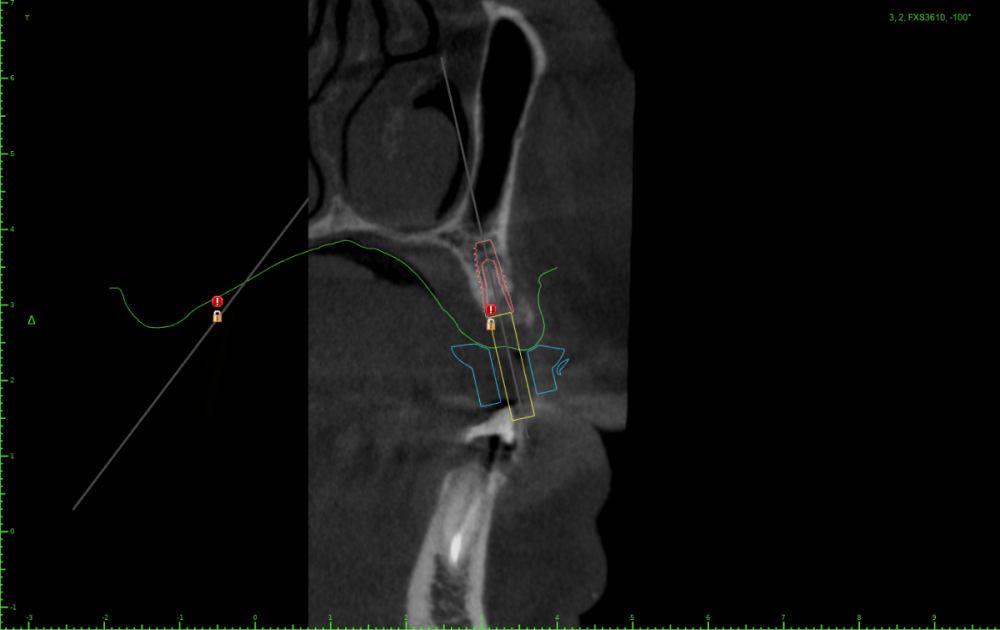

АнтонТЛТ Опубликовано 25 июля, 2023 Поделиться Опубликовано 25 июля, 2023 Значит пора выложить скрины проекта шаблона) посмотреть что там с параллельностью, если там всё параллельно, тогда искать причину почему имплантаты завалены Ссылка на комментарий

Женька Опубликовано 25 июля, 2023 Автор Поделиться Опубликовано 25 июля, 2023 23 часа назад, Женька сказал: Но буду честен, можно было чутка 1.4 наклонить и сооснопоставить. я же уже говорил об этом. Вот если бы параллелил по 1.6 . Как по мне так себе позиция Поэтому выбрана такая И соответственно если бы параллелил по 1.4 Ссылка на комментарий

АнтонТЛТ Опубликовано 25 июля, 2023 Поделиться Опубликовано 25 июля, 2023 А сагиттальный срез? Ссылка на комментарий

АнтонТЛТ Опубликовано 25 июля, 2023 Поделиться Опубликовано 25 июля, 2023 По фото выглядит так как будто установлены так Ссылка на комментарий

Женька Опубликовано 26 июля, 2023 Автор Поделиться Опубликовано 26 июля, 2023 (изменено) @АнтонТЛТ , не, не делали. Через полгодика сделаю, как раз пластика с другой стороны (сетка, которую выкладывал) должна созреть.) Возможно из-за синуса ось сместилась ну и были определённые проблемы привязки КТ и скана. Зубы есть, но программа не хотела даже по точкам сопоставлять. Пришлось в ручную. саггиталь не могу выстроить как не кручу, чтобы оба болта попали. Изменено 26 июля, 2023 пользователем Женька Ссылка на комментарий